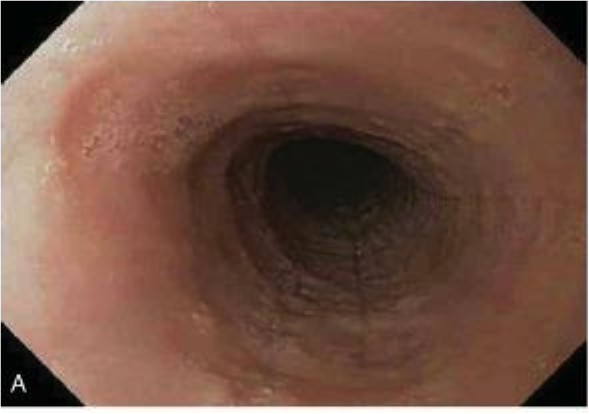

normal gastroesophageal junction

stratified sqaumous of esophagus

simple columnar of gastric cardia

GERD

Hyperemia, vertical linear streaks represent superficial mucosal erosions/ulcers

GERD on bottom

squamous proliferation, papillae elongation, basal cell hyperplasia, inc. inflammation in lamina propria, decreased surface maturation

Note: biopsy findings are not specific! cannot make diagnosis w/ biopsy alone must have clinical info as well